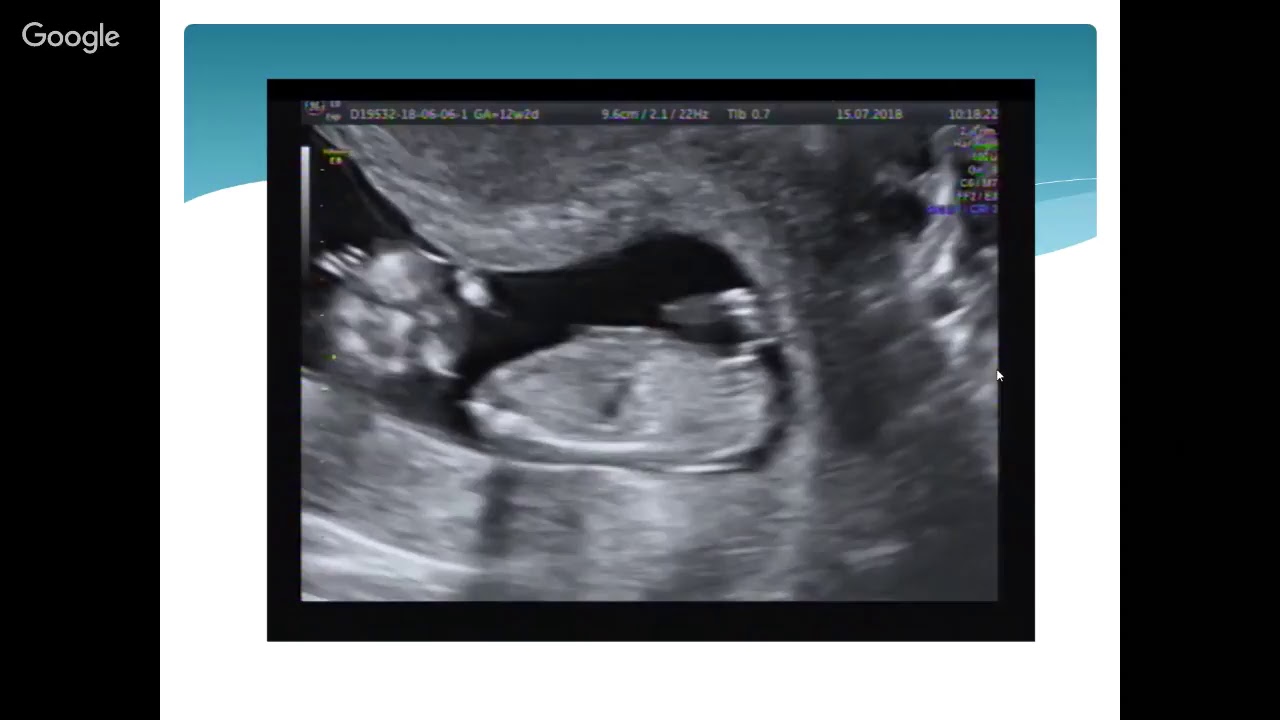

Чем больше срок, тем более полную картину показывает исследование – врач констатирует наличие не только плодного яйца, но и желточного мешочка в нем, или же даже увидит эмбрион и его сердцебиение, и сможет померить КТР эмбриона (расстояние от копчика до темечка).

- Во втором триместре оценка сроков проходит методом замеров отрезков между анатомическими ориентирами, а также размеров головы, живота и т.д. Отдельное внимание стоит уделить копчико-теменному индексу (КТР). Он представляет собой отрезок, проведенный между копчиком и головным концом. КТР позволяет определить не только длину, но и вес. Для его оценки применяются специальные таблицы, которые включают в себя возможность отклонения показателя из-за конституциональных особенностей ребенка.

Уже начиная с 5‒6 недели значимость выяснения представленного параметра снижается. На смену приходит оценка копчико-теменного размера (КТР). Диаметр плодного яйца продолжают определять до 8‒9 недели при исследовании трансабдоминально. Это связано с тем, что детальная визуализация и измерение КТР таким способом затруднительны.

Последний метод обладает большой точностью определения срока беременности, особенно на 11‒13 неделях.

как высчитывают КТР.

Именно в этот период рекомендовано проводить первое скрининговое обследование. Данные кардиотокографии в зависимости от недели «интересного положения» представлены ниже.

Копчико-теменной размер является основным показателем. Он используется в ультразвуковом сканировании для определения срока гестации. Точность параметра обусловлена тем, что он имеет минимальную зависимость от внешних и внутренних факторов (раса, физические данные родителей, состояние здоровья матери и др.).